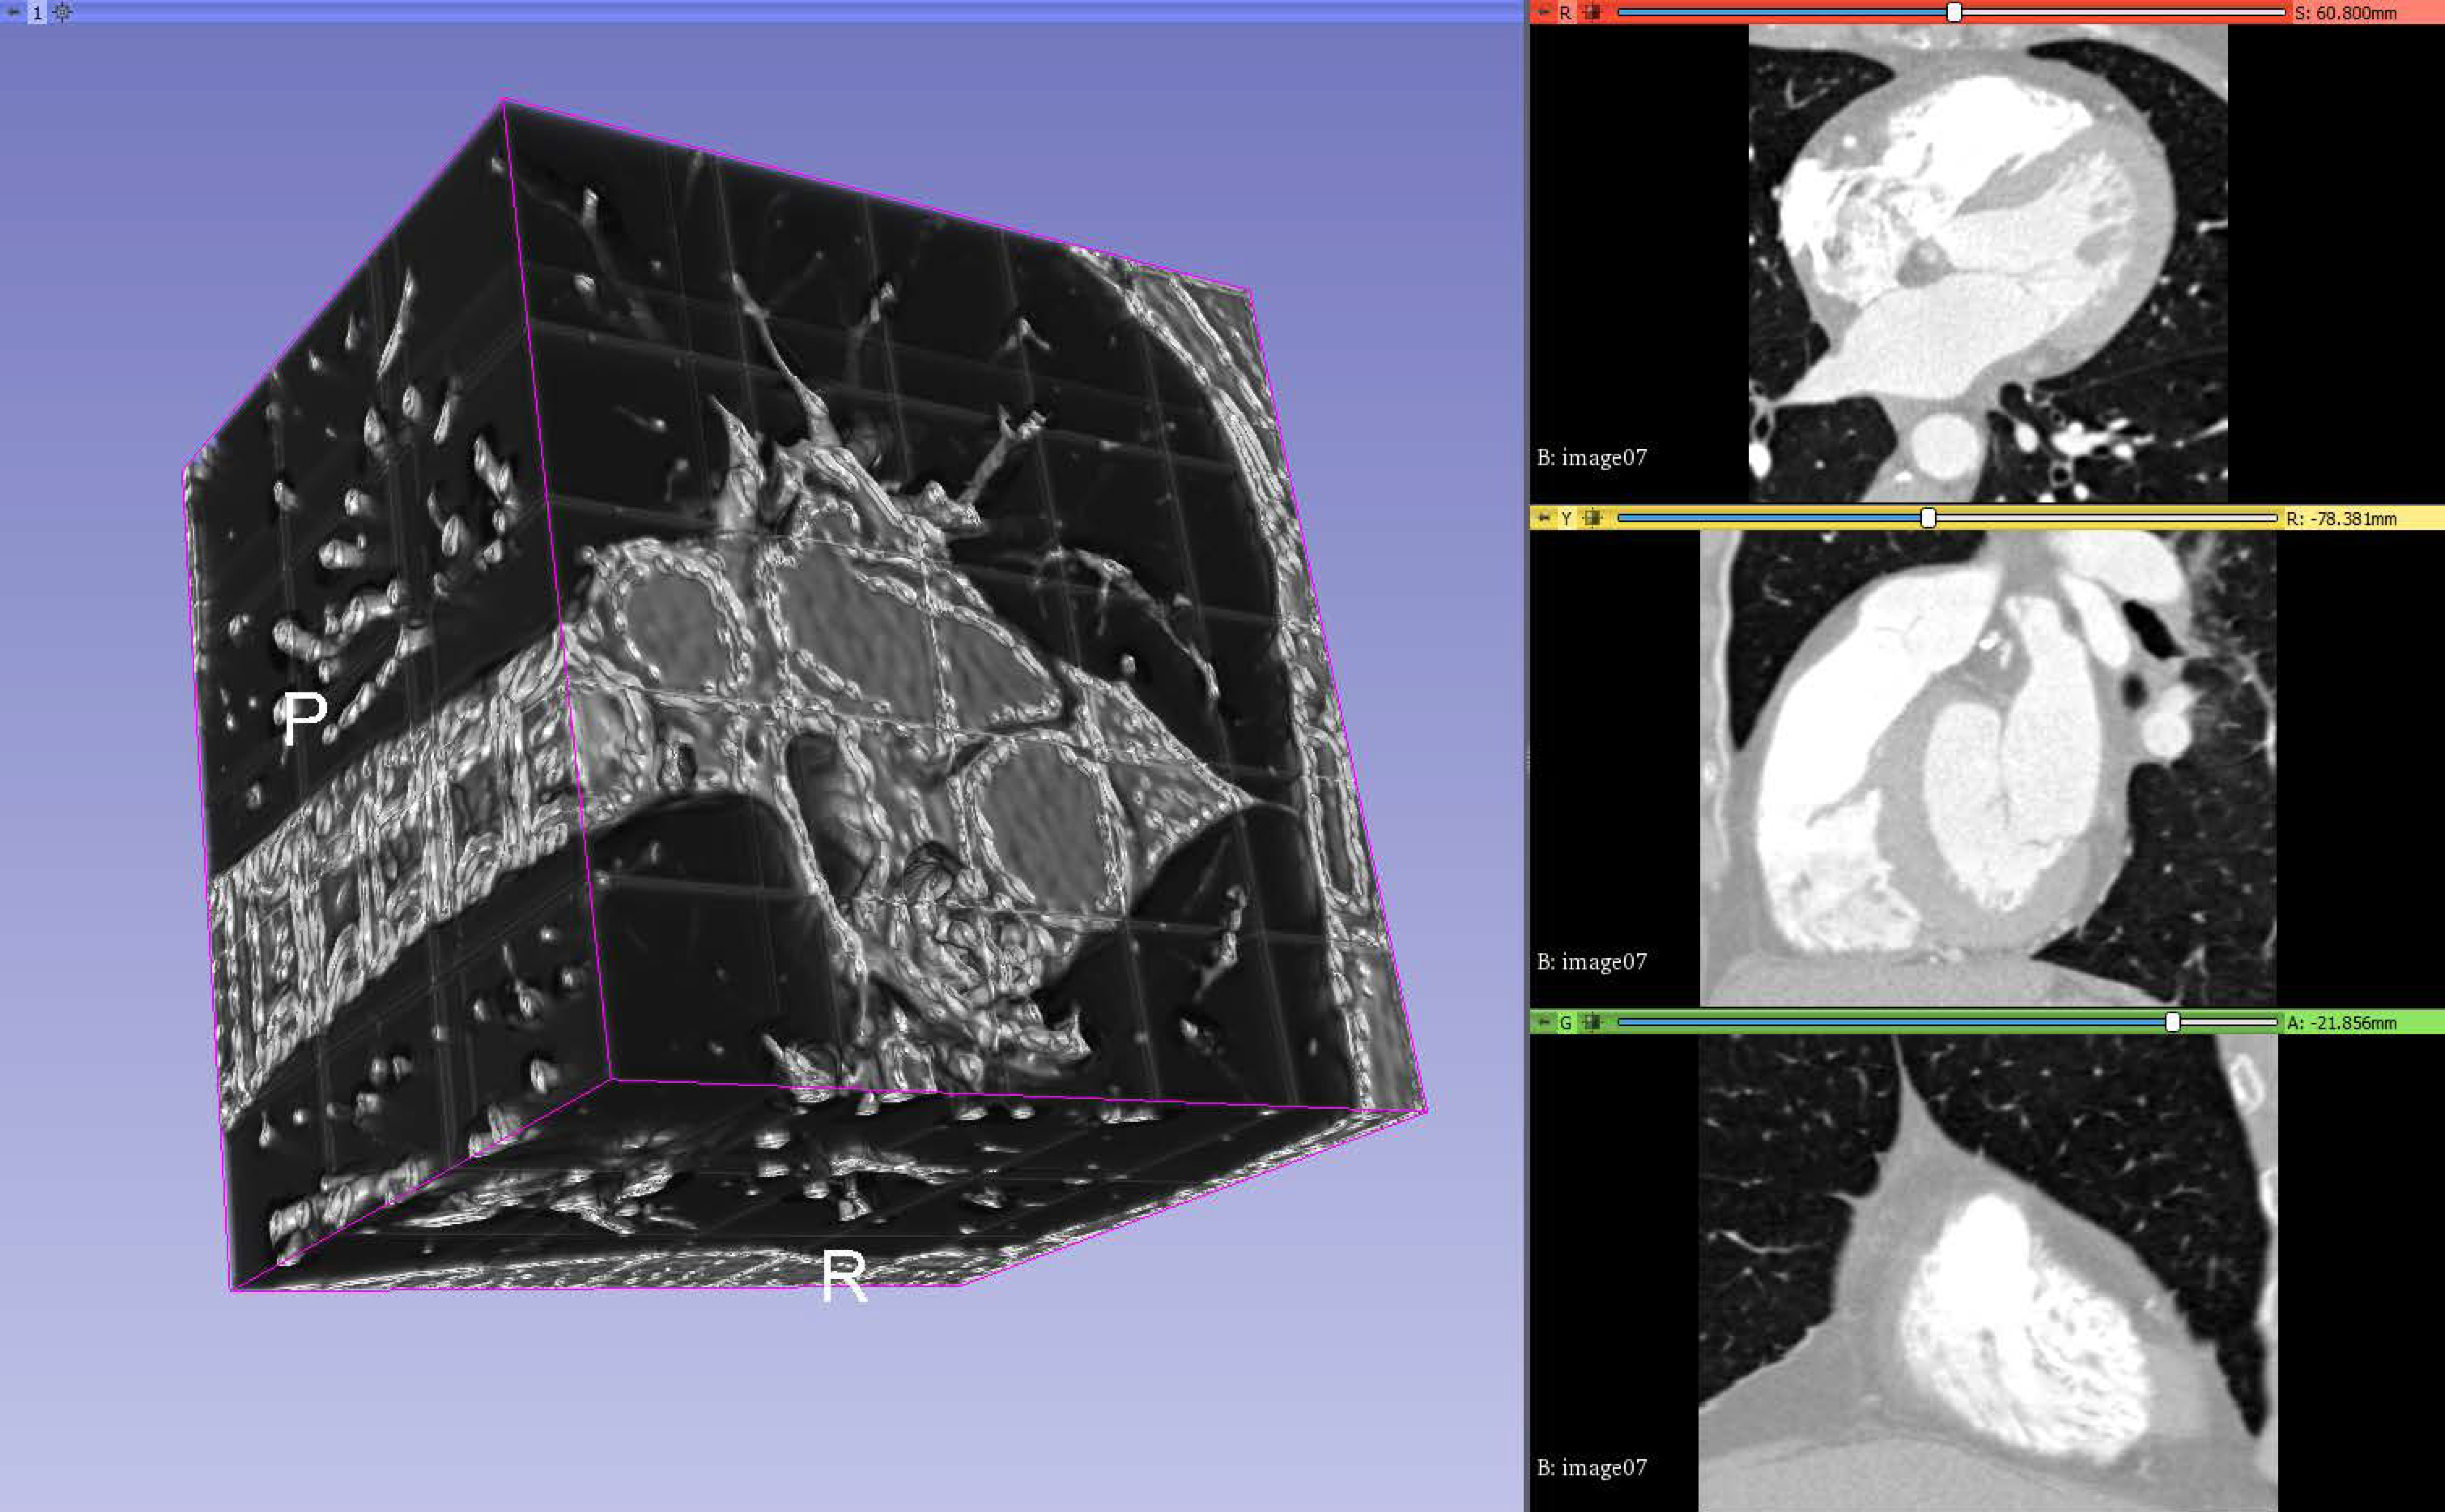

The result is exported as a 3D volume in the same format as the input volumes and generated input masks so that it can be loaded by similar software. One can observe in Figure 4 the output volume composed of patches, in which the threshold is lowered to make it clear where the patches meet.

Figure 4.

Output volume composed of patches with visible stitching.